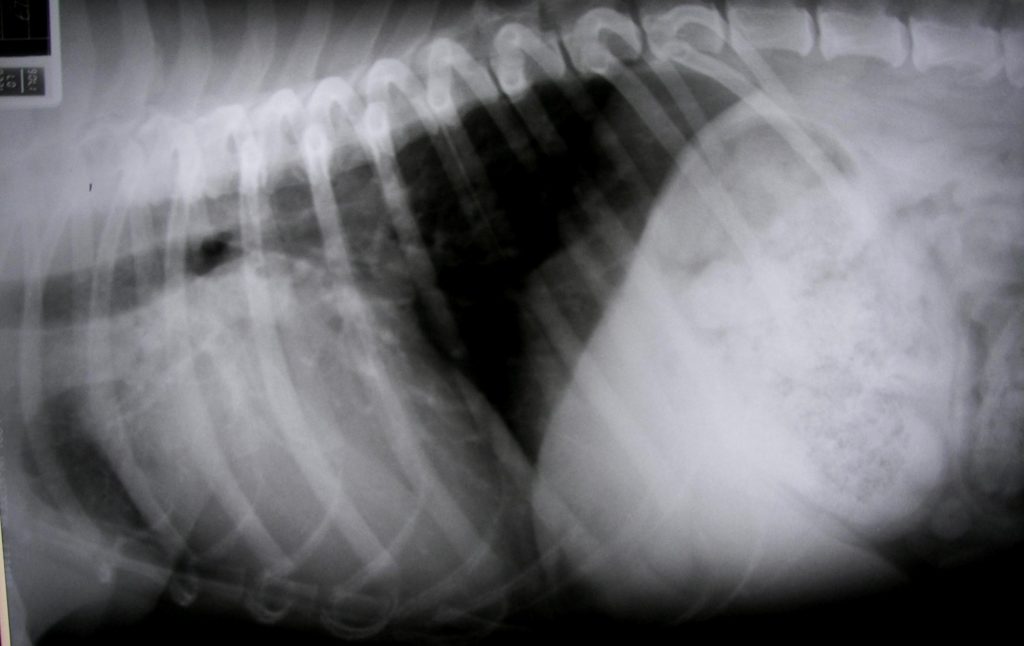

Un paciente mestizo (cruzado), macho, de 12 años, 17 kg de peso, con grado moderado de obesidad, mal estado de higiene oral, vacunado y desparasitado, con alimentación balanceada comercial (seca, pienso, estrusionado) y sin otras anomalías aparentemente relacionadas, se presenta en la consulta para su revisión. Se detectaron un soplo mitral sistólico grado IV/VI, tos seca no productiva, fatiga e intolerancia al ejercicio físico y al estrés, apatía y pérdida moderada de apetito.

El diagnóstico presuntivo fue de insuficiencia cardíaca congestiva por enfermedad mitral –valvulopatía aurículo-ventricular degenerativa mixomatosa crónica-, se tomó un ECG que mostraba una taquicardia sinusal sostenida con una frecuencia de 180 lpm pero sin otras alteraciones de consideración. Se determinó serología de dirofilaria immitis que fue negativa.

Actualmente la situación del paciente es similar a la inicial pese al tratamiento, más decaído, con más tos y frecuencia cardiaca de 180 lpm. Frecuencia respiratoria de 45 rpm, temperatura rectal 38,2 ºC y tiempo de relleno capilar > 2 s.

A la vista de su radiografía torácica en posición lateral derecha:

¿Cuál sería nuestra primera impresión/diagnóstico presuntivo/recomendación de tratamiento?